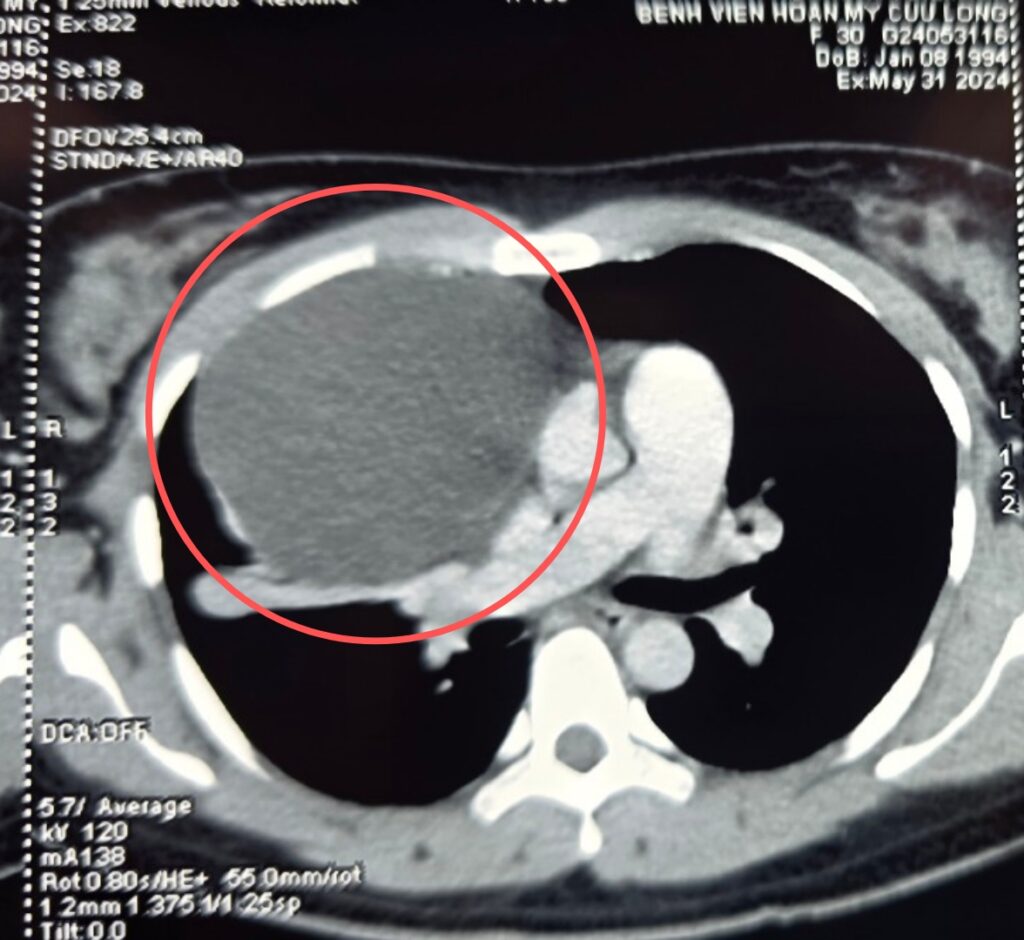

Các bác sĩ Bệnh viện Hoàn Mỹ Cửu Long vừa phẫu thuật nội soi lồng ngực cắt bỏ khối u nang trung thất khổng lồ chèn ép tim phổi. Bệnh nhân là chị D.T.D.M (30 tuổi, địa chỉ tại huyện Long Phú, tỉnh Sóc Trăng) nhập Bệnh viện Hoàn Mỹ Cửu Long vì ho khan, […]